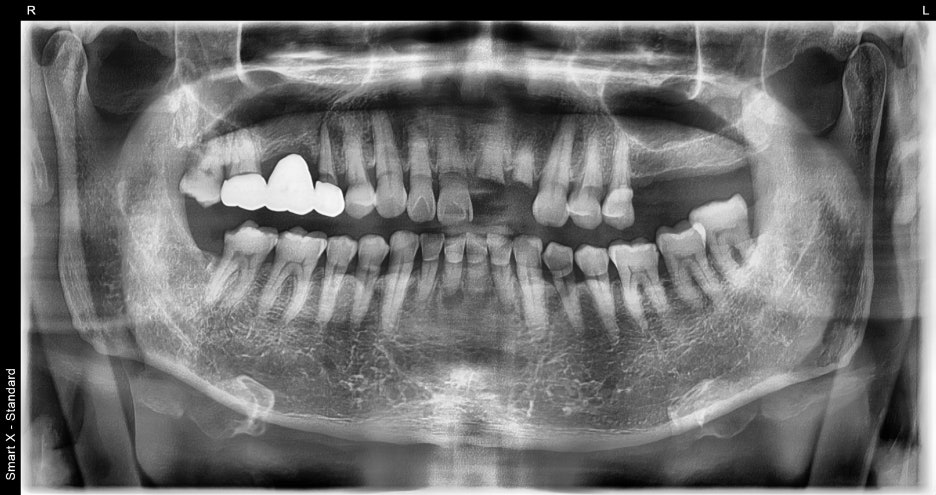

진단결과

정밀 진단 결과

입술·잇몸 열상 → 봉합술 필요

상악 앞니파절 및 발치 필요

하악 앞니 손상으로 발치 필요

잇몸과 치조골 상태는 전반적으로 양호하여

임플란트 식립 가능이라는 결과가 나왔습니다.